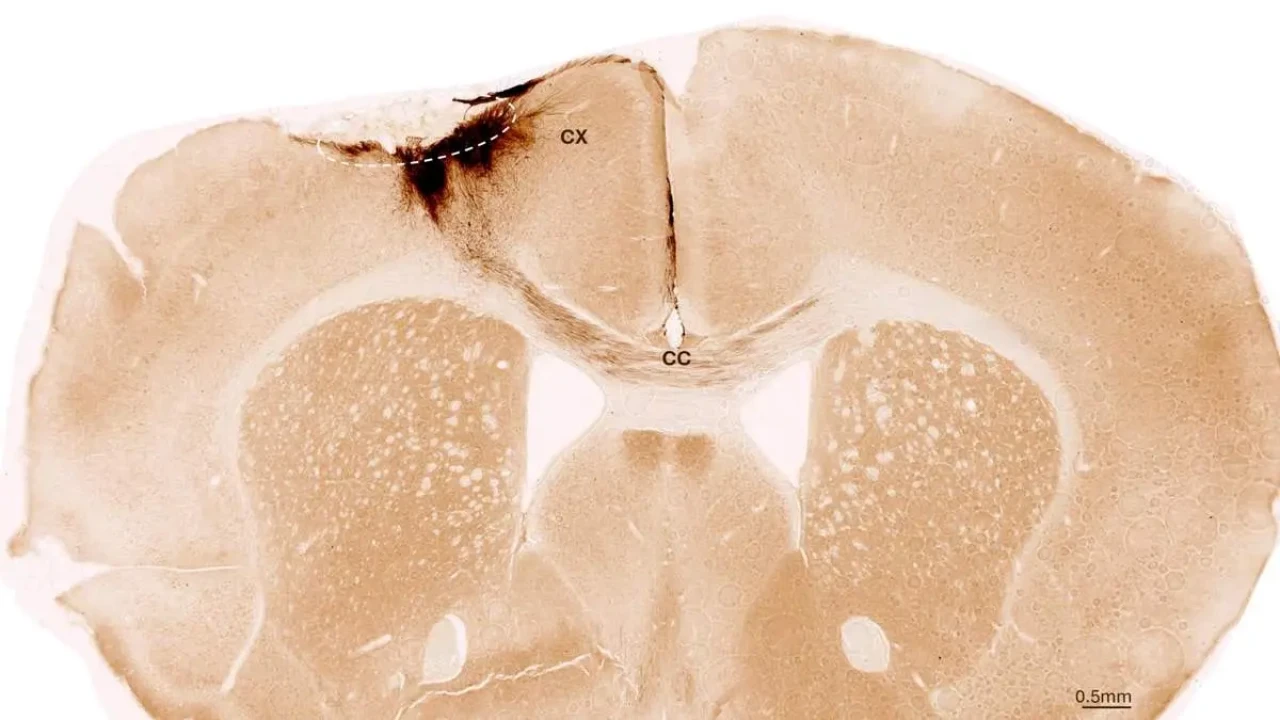

یک هفته پس از القای سکته، تیم تحقیقاتی سلول‌های بنیادی عصبی را به ناحیه آسیب‌دیده مغز پیوند زدند و با استفاده از روش‌های تصویربرداری و بیوشیمیایی مختلف، روندهای بعدی را بررسی کردند. تاکنبرگ می‌گوید: «ما دریافتیم که سلول‌های بنیادی در طول دوره پنج‌هفته‌ای تحلیل زنده ماندند و بیشتر آن‌ها به نورون تبدیل شدند؛ نورون‌هایی که حتی با سلول‌های مغزی موجود ارتباط برقرار کردند.»

پژوهشگران همچنین نشانه‌های دیگری از بازسازی را مشاهده کردند: تشکیل رگ‌های خونی جدید، کاهش فرآیندهای التهابی، و بهبود یکپارچگی سد خونی-مغزی. تاکنبرگ توضیح می‌دهد: «تحلیل ما فراتر از محدوده مطالعات دیگر است که فقط بر اثرات فوری پس از پیوند تمرکز داشتند.» خوشبختانه، پیوند سلول‌های بنیادی در موش‌ها همچنین اختلالات حرکتی ناشی از سکته را معکوس کرد. بخشی از اثبات این موضوع از طریق تحلیل حرکتی موش‌ها با کمک هوش مصنوعی به‌دست آمد.